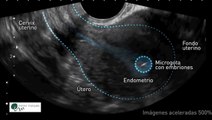

Los científicos han logrado un avance revolucionario al crear embriones humanos sintéticos a partir de células madre.

Se trata de un avance completamente sintético, que prescinde de la necesidad de esperma u óvulos.